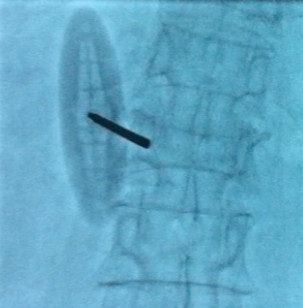

Специальная игла для вертебропластики. Обеспечивает легкое и эффективное проникновение не только через мягкие ткани, но и в костную ткань благодаря уникальной заточке на тыльной стороне иглы. Имеет Luer-Lock. Рукоять удобной овальной формы, ось которой имеет угол наклона по отношению к оси иглы. Данная особенность оптимально отражает анатомию кисти человека и исключает неестественную постановку сустава кисти при вкручивании иглы. Игла полностью рентген прозрачна по всему корпусу, включая рукоять, что обеспечивает высокий контроль за продвижением и размещением цемента.

Игла BBLV отличается от Vertebro только тем, что рентген-прозрачна только пластиковая рукоять иглы. Других конструктивных отличий нет.